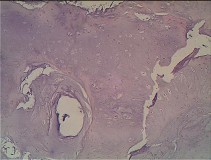

Figures 7a through 7d are the radiograph, MR images, and biopsy specimen of a 35-year-old man who has a painful, slowly enlarging knee mass. Which chromosomal translocation is characteristic of this pathology?

Synovial sarcoma is a soft-tissue sarcoma that usually occurs in young adults. Synovial sarcoma often causes pain, unlike most soft-tissue sarcomas, which generally do not cause pain. Imaging characteristics include soft-tissue calcifications on plain radiographs and a heterogeneous mass that is generally isointense to muscle on T1-weighted images and hyperintense to muscle on T2-weighted images. There are biphasic and monophasic types of synovial sarcoma. The biphasic

type, which is depicted here, has both spindle cell and epithelial components and will stain for both vimentin and cytokeratin. More than 90% of patients with synovial sarcoma have a characteristic genetic translocation of t(X;18), which results in the fusion protein SS18-SSX. This translocation can be stained for use of florescence in situ hybridization technology. t(11;12) is seen in Ewing sarcoma. T(9;22) is seen in extraskeletal myxoid chondrosarcoma. t(12;16) is seen in myxoid liposarcoma.